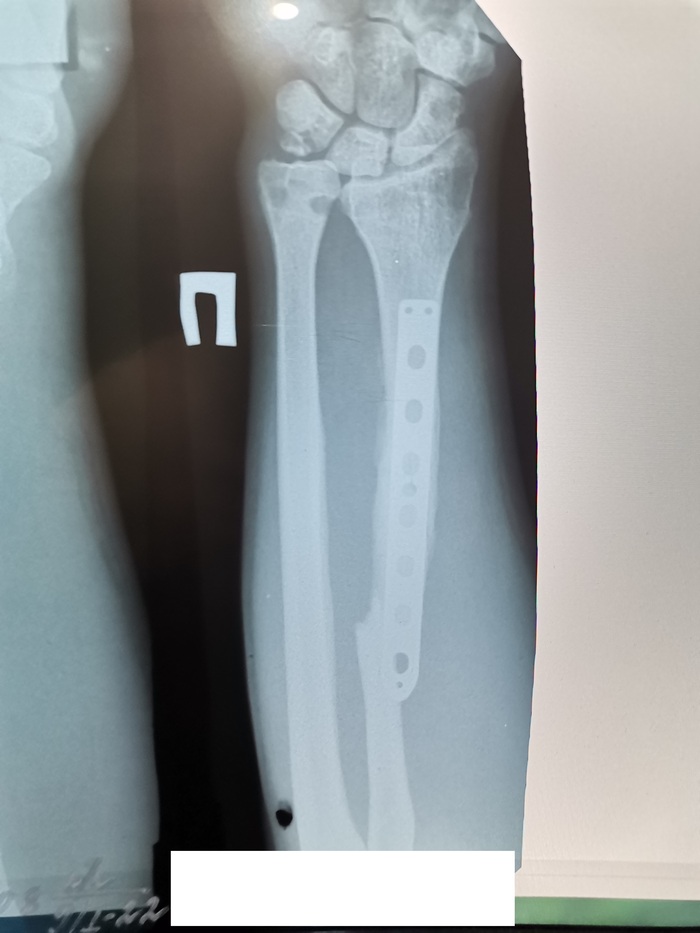

И вот я увидел этот пост на Пикабу и решил обратиться к докторам. Приехал на первичный осмотр, где меня осмотрели, дали консультации, направили на исследования. Результаты исследований оказались не самыми радужными. Было принято решение о 4-й операции.

Я пришёл на повторный осмотр. Где мне всё рассказали, объяснили, успокоили и пообещали помочь. Был назначен день операции

За день до операции я прибыл в клинику. Меня встретил вежливый персонал, великолепная палата и отличные условия. В клинике я пролежал 2 дня. На 2-й день была сделана операция, на которой мне провели невролиз глубокой ветви правого лучевого нерва. Результат не заставил себя долго ждать. уже через 3 дня мои пальцы снова зашевелились.